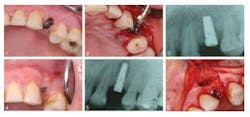

Oral implant surgery is complex and not without complications, one of which is an implant periapical lesion (IPL). If the lesion site becomes infected, it can lead to an abnormal growth, persistent inflammation and tenderness. However, a procedure that allows complete bone regeneration at the implant related lesion site shows promise in treating the resulting bone defect and infection.ADDITIONAL READING |Study finds that shorter waiting time between dental procedures is adequate IPL develops rapidly after implant surgery and is treated with a second reparative surgery, in combination with antibiotic use. Surgeons have tried various treatments, such as using hand tools to enucleate the lesion, placement of bovine bone mineral to replace the diseased bone, and using an enamel mixture to help strengthen the surrounding tissues. Results from these treatments have been mixed. Some treatments have been successful, while others resulted in the lesion progressing, and in others the implant was lost.ADDITIONAL READING |Atrophic patients have more options with new dental implant In a Journal of Oral Implantologycase study titled “Active implant periapical lesion: a case report treated via guided bone regeneration with a five-year clinical and radiographic follow-up,” surgeons reported on using guided bone regeneration (GBR) principles to completely remove the lesion and any subsequent infections.

A 43-year-old female presenting with a symptomatic left, first premolar was a candidate for dental implant treatment and scheduled for an immediate implant placement following tooth extraction. After surgery she was prescribed antibiotics. She was seen three months later due to pain at the implant site, which revealed a sinus tract related to the implant. Additionally, there was a “soft spot” due to edema and bone loss. She was prescribed another course of antibiotics and returned in four days. At that time, a tetracycline paste was created and placed on the defect and around the implant for three minutes, then removed. In two months, a transitional crown was placed, with placement of the final six months later. At the subsequent one-, two-, six-month, one- and five-year appointments, no pain was reported and complete bone fill (see photo below) in to the previous lesion area was stable.